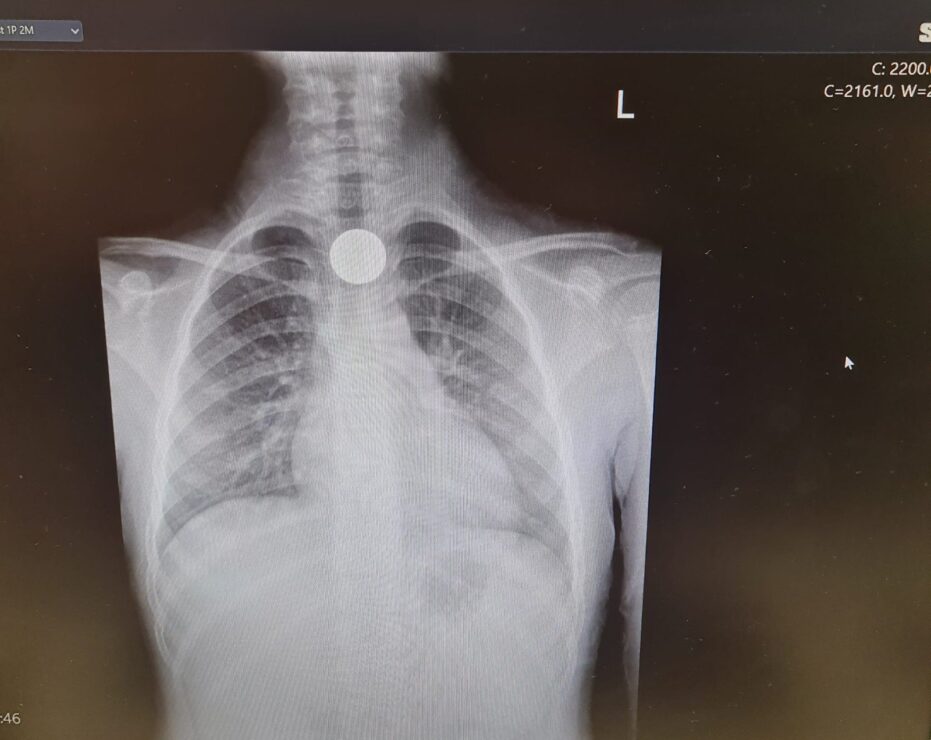

כהן הללי, ילדה בת 6 וחצי מאשקלון, בלעה אתמול מטבע של 10 אגורות בבית הספר. הללי הגיעה למיון, נשלחה לצילום, שבו נצפה מטבע בוושט. המטבע הוצא בפעולת גסטרוסקופיה. הללי התאוששה ושוחררה לביתה במצב טוב.